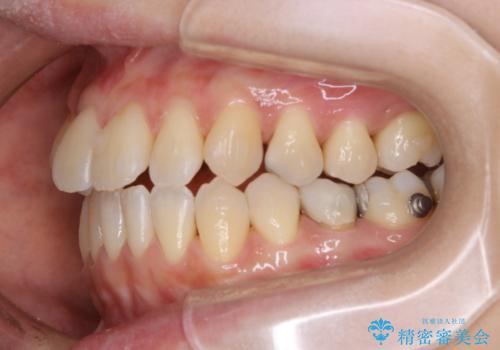

マウスピース矯正インビザライン治療では、歯の表面にアタッチメントという突起を設定します。(アタッチメントは歯の動きを効率的に移動するためのものです)

アタッチメントが歯に付くと、表面が凸凹し磨き残しが多くなったりと、プラークや歯石・着色がつきやすくなることがあります。

矯正治療中もPMTCを定期的に行い、専門的な機械でしっかりと汚れを除去することがおススメです。